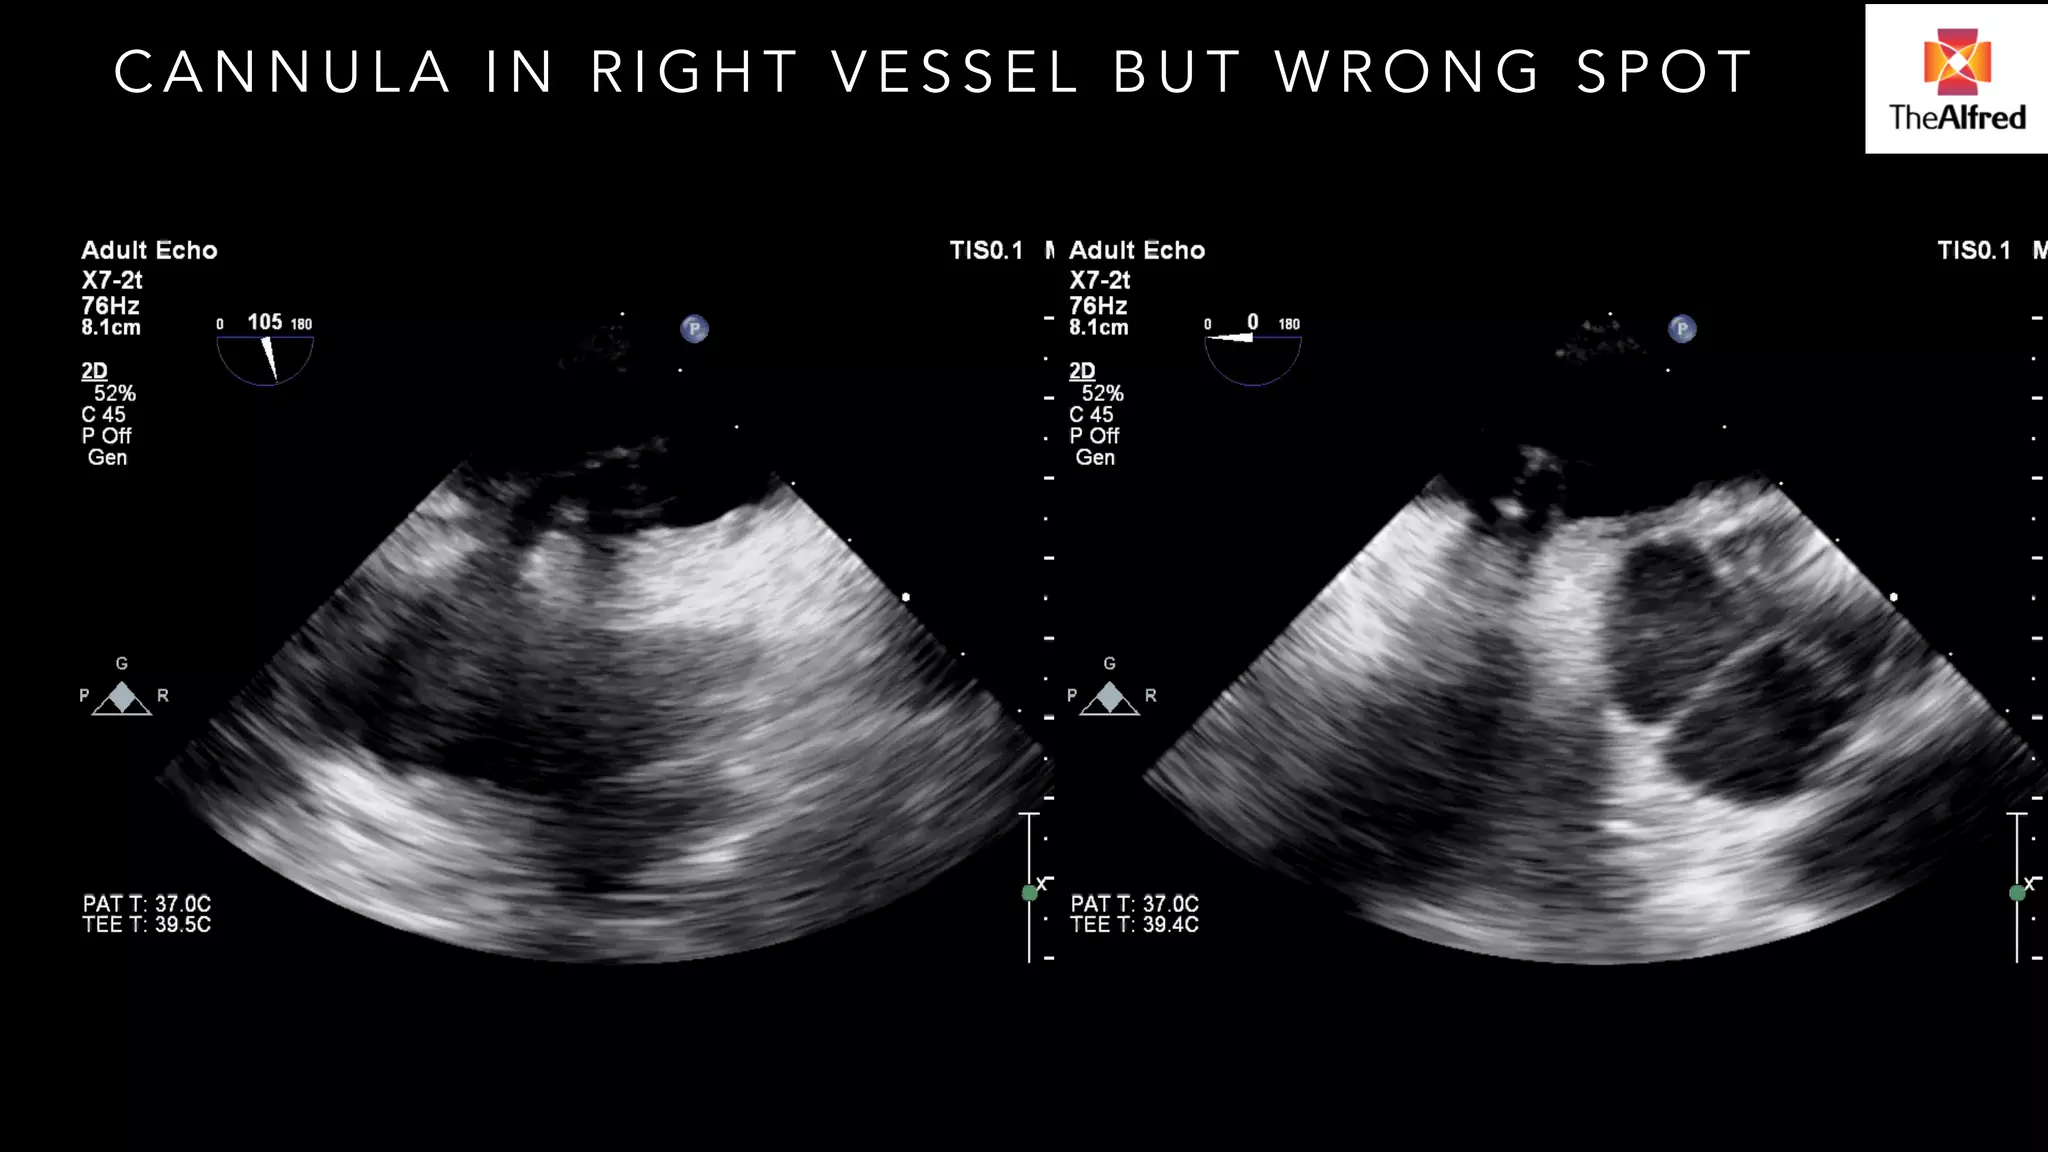

CANNULA IN RIGHT VESSEL BUT WRONG SPOT

CANNULA IN RIGHTVESSEL BUT WRONG SPOT

TROUBLESHOOTING CANNULA PROBLEMS Not always easy Percutaneous cannulation in shocked patient Cardiogenic shock complicating cardiac surgery necessitating return to OR

CANNULATION Complicated bypresence of IABP V shocked patient Seemed to go smoothly

POST CANNULATION Highpressures in ECMO circuit limiting support Ultrasound of cannulas- in vessels Venous cannula appropriately placed